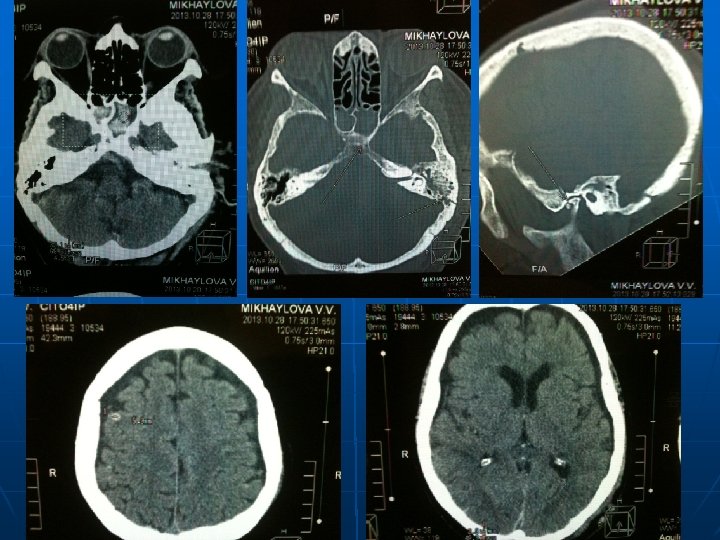

Проведен комплекс лабораторных и диагностических мероприятий n n n n общий анализ крови (Нв – 91 г/л) общий анализ мочи биохимический анализ крови + электролиты (Общий белок – 59 г/л) газовый состав крови ( Pa. CO 2 -30, 4, Pa. O 2 – 58, 3) Коагулограмма (МНО - 1, 18, АЧТВ – 25, 3, тромбоциты – 193*10/л) ЭКГ рентгенограмма органов грудной полости КТ-головы, груди

Диагноз: Основное заболевание: Тяжелая сочетанная травма головы, груди. ОЧМТ. Линейный перлом чешуи затылочной кости слева с переходом на чешую левой височной кости и на основание черепа( левую пирамиду). Перелом клиновидной кости. Ушиб головного мозга средней степени тяжести с формированием контузионных очагов в правых лобной, височной, теменной зонах, левом таламусе. САК. Ушитая рана левой теменной области. Закрытая травма груди. Множественные переломы ребер. Ушиб обоих легких. Двусторонний гидроторакс. Осложнения: Острая дыхательная недостаточность 2 ст. Сопутствующая патология: Ишемическая болезнь сердца. Атеросклероз коронарных сосудов. Гипертоническая болезнь 2 ст.